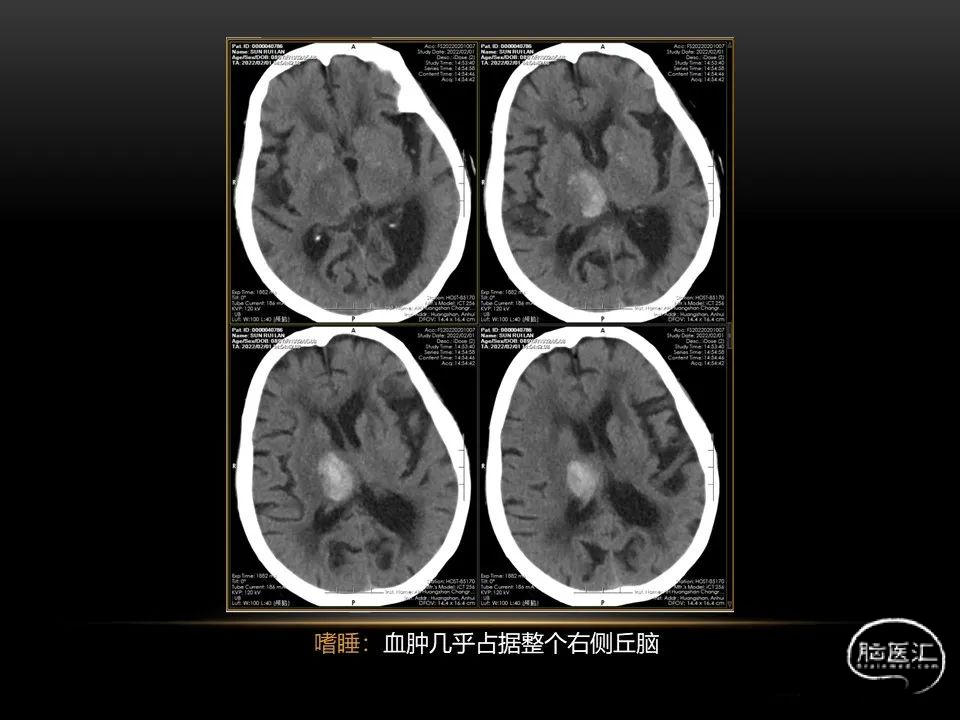

自发性脑出血临床上很常见,不同原因有特征性的出血部位。例如:基底节出血和丘脑出血大多是高血压性脑出血;脑叶出血,特别是多次复发的脑叶出血多见于老年人的脑血管淀粉样变。

自发性脑出血不仅仅累及内囊后肢才会出现偏瘫及偏身感觉障碍,病变累及大脑脚或辐射冠同样有可能有类似症状和体征。内囊、辐射冠、大脑脚等结构之间是延续的,只是不同区域不同名称而已。定位诊断需要对解剖结构概念清晰,读片准确辨认,灵活掌握。